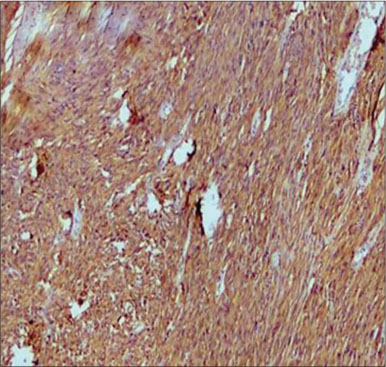

A total of 90 mesenchymal tumors of the GIT and pancreas diagnosed in SKIMS from January 2010 to December 2016 were reclassified on the basis of morphologic features and IHC into 77 (85.6%) cases of GIST and the remaining 13 (14.4%) cases as other mesenchymal tumors. The mesenchymal tumors included five cases of inflammatory myofibroblastic tumors, two cases of leiomyoma, four cases were sarcomas, one case was poorly differentiated carcinoma, and one was desmoid tumor. C-KIT positivity was seen in 72 (93.5%) cases and DOG 1 was positive in 77 (100%) cases [Figures 1], [2], [3], [4]. However, the correlation between DOG1 and CKIT was found to be statistically insignificant (P = 0.23). There was no significant association between DOG 1 expression and various histopathological parameters in the studied cases. Clinicopathological variables have been enumerated in [Table 1].

| Figure 4 Discovered on gastrointestinal stromal tumor 1 staining